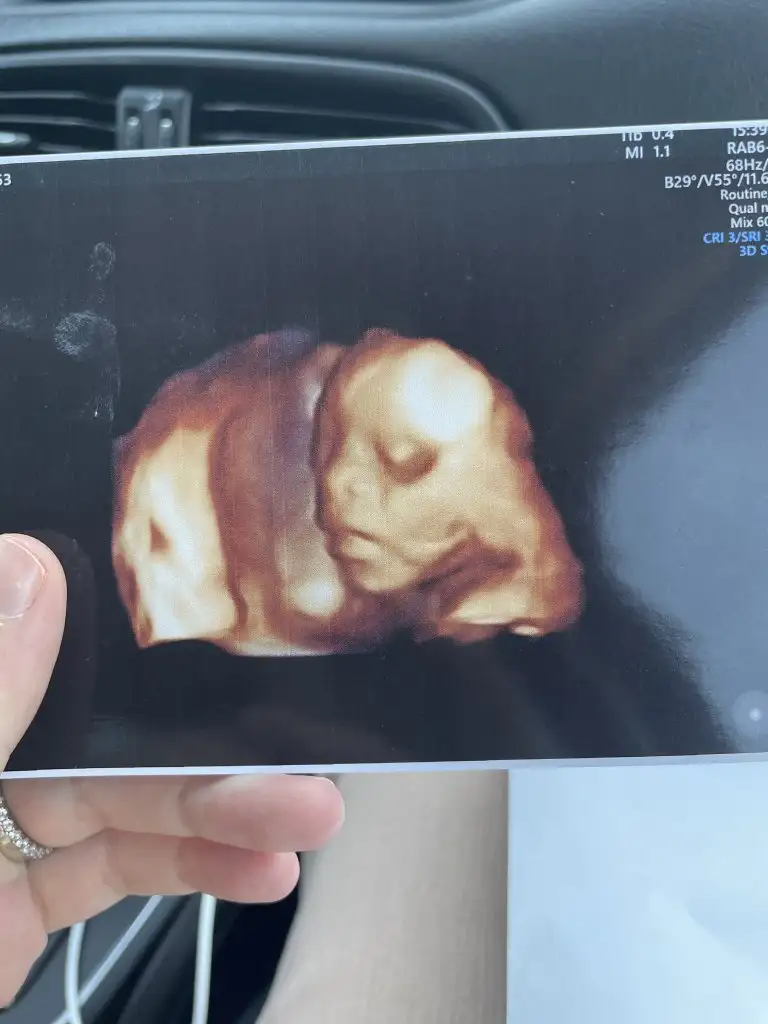

Çıktım canım, herşey yolunda şükür. 5 güm önden gidiyor. 500 gram 26 cm. Plesenta önde olduğu için geç hissetmişim. Çok zor gösterdi bebek yüzünüCanimmm naptin

Yaaa yerim buneeeeggggÇıktım canım, herşey yolunda şükür. 5 güm önden gidiyor. 500 gram 26 cm. Plesenta önde olduğu için geç hissetmişim. Çok zor gösterdi bebek yüzünü